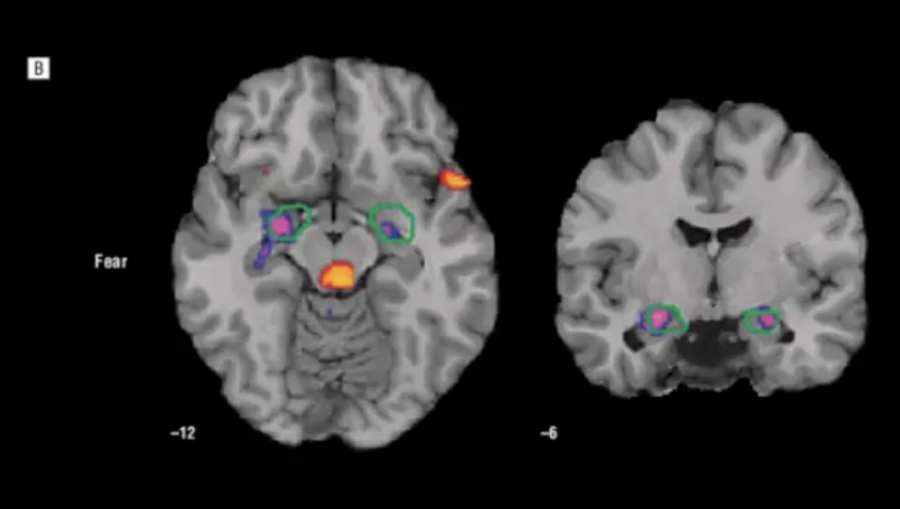

на само формирование чувства страха влияют десятки нейронных систем и сенсорных входов, но изначально ощущение тревоги и опасности исходит из одной из областей нашего мозга — миндалевидного тела, — амигдалы.

fMRI (МРТ) активности амигдалы на примере клинического пациента для демонстрации её структуры. фиолетовый оттенок указывает на сами зоны активности, а зелёная обводка — на протяженность исследуемых при fMRI областей

Сама по себе, амигдала — это маленькая, парная структура, находящаяся в белом веществе височной доли полушарий мозга.

По сути, миндалевидное тело является своеобразным «детектором угрозы». получая грубую сенсорную информацию почти напрямую, оно запускает физиологические реакции страха ещё до того, как подключится логическое мышление коры головного мозга.